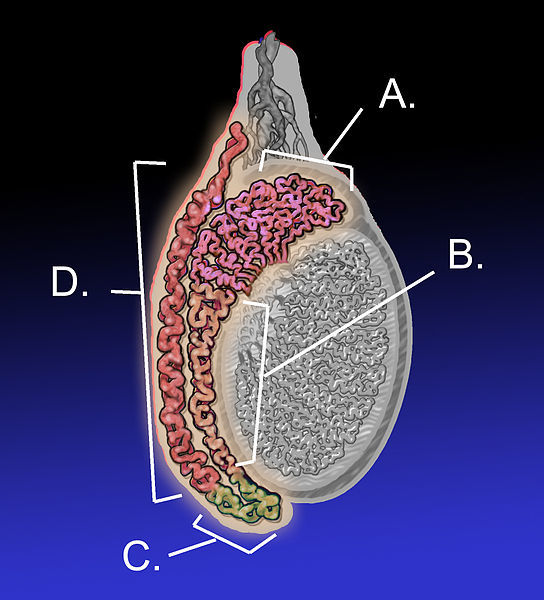

Epididymis anatomy

• A - head of epididymis

• B - body of epididymis

• C - tail of epididymis

• D - vas deferens